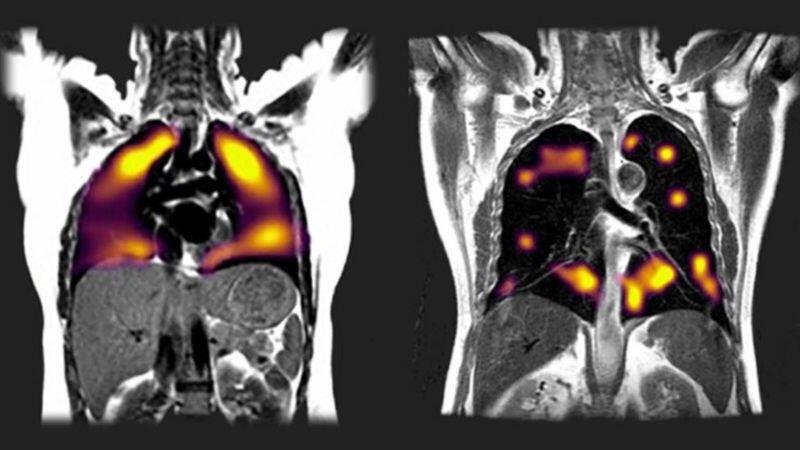

Solda sağlıklı akciğer, sağda ise Covid nedeniyle hasarlanmış akciğer görülüyor. Sağdaki daha büyük siyah bölgeler, oksijenin yeterince kana aktarılamadığını gösteriyor.

Ksenon gazıyla yapılan taramalarda ise bu hastalarda akciğer hasarı belirtilerine rastlandı. Kana rahat oksijen akışı olmayan bölgeler tespit edildi.

Bu yeni tarz EMAR'da (manyetik rezönans görüntüleme) ksenon (zenon) gazı kullanılarak akciğerdeki hasarın kapsamı tespit ediliyor.